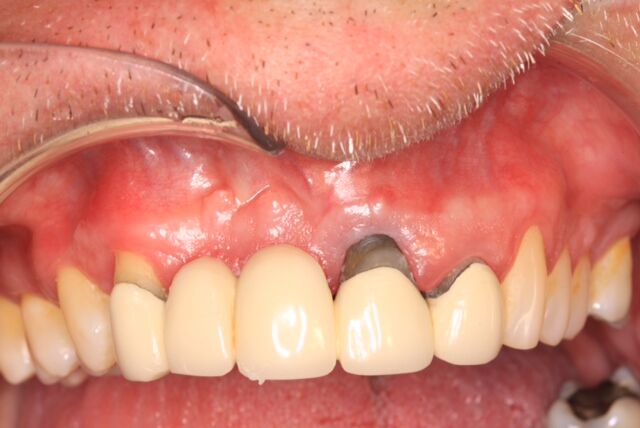

(10.) Initial clinical evaluation of Nos. 12 through 14 after crown on No. 12 and pontic on No. 13 removed.

Figure 10

(14.) Integration confirmation on Nos. 12 and 13 at 6 months with temporary abutments and good soft tissue maturation.

Figure 14

(15.) Clinical view of final individual crowns on Nos. 12 and 13.

Figure 15

(16.) Radiograph of final restorations on Nos. 12 and 13. Notice platform shift in No. 12 restoration.

Figure 16

A 67-year-old woman presented on an emergency basis with a bad odor and taste from crown No. 12, which had been diagnosed that day at hygiene recall as decayed and no longer attached to the underlying root (Figure 8 and Figure 9). The patient was anesthetized and the existing bridge was sectioned (Figure 10), leaving crown No. 14 intact. The No. 12 root was extracted and the site was fully debrided of granuloma. A platform shift implant was stabilized in excess of 45 Ncm in position No. 12, which was prosthetically correct. The soft tissue of pontic site No. 13 was contoured to mimic soft tissue contours of a bicuspid and an implant was secured in excess of 45 Ncm. Implant No. 13 was milled to allow for unimpeded seating of the temporization abutment, whereas implant No. 12 did not need milling as it was a platform-shift implant. The existing crown No. 12 and cantilever No. 13 were revised to be a temporary bridge on Nos. 12 and 13 (Figure 11 and Figure 12). The revised temporary bridge was positioned in infraocclusion and cemented after the extrusion of excess cement extraorally (Figure 13). No bone graft or sutures were placed as the temporary crowns sealed the sockets.

The patient was prescribed antibiotics and analgesics and instructed in postoperative care particular to immediately provisionally restored implants. At 6 months, integration was confirmed (Figure 14) and the patient returned to her dentist for restoration. The implants were restored with individual cement-retained crowns with a platform shift for No. 12 restoration from the 6-mm diameter of the implant to a 5-mm diameter of the final restoration (Figure 15 and Figure 16).